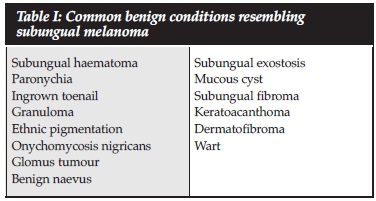

Pigmentation of the toenails can be due to benign, systemic disease manifestation or malignant conditions, with melanoma being one of the rare malignancies (3.2% of foot and ankle tumours).8,9 Generally there are four types of melanoma, with acral melanoma affecting the hands and feet. This usually occurs in black African and Asian populations contrary to the other types which are more common in fair-skinned populations.7,9 Delayed diagnosis of subungual melanoma is largely due to misdiagnosing the lesion as being benign (Table I).4,812 Table II shows all case reports of subungual amelanotic melanoma affecting the hallux, all of which had a delay in the diagnosis. Only five case reports were identified after an extensive search of the English literature.